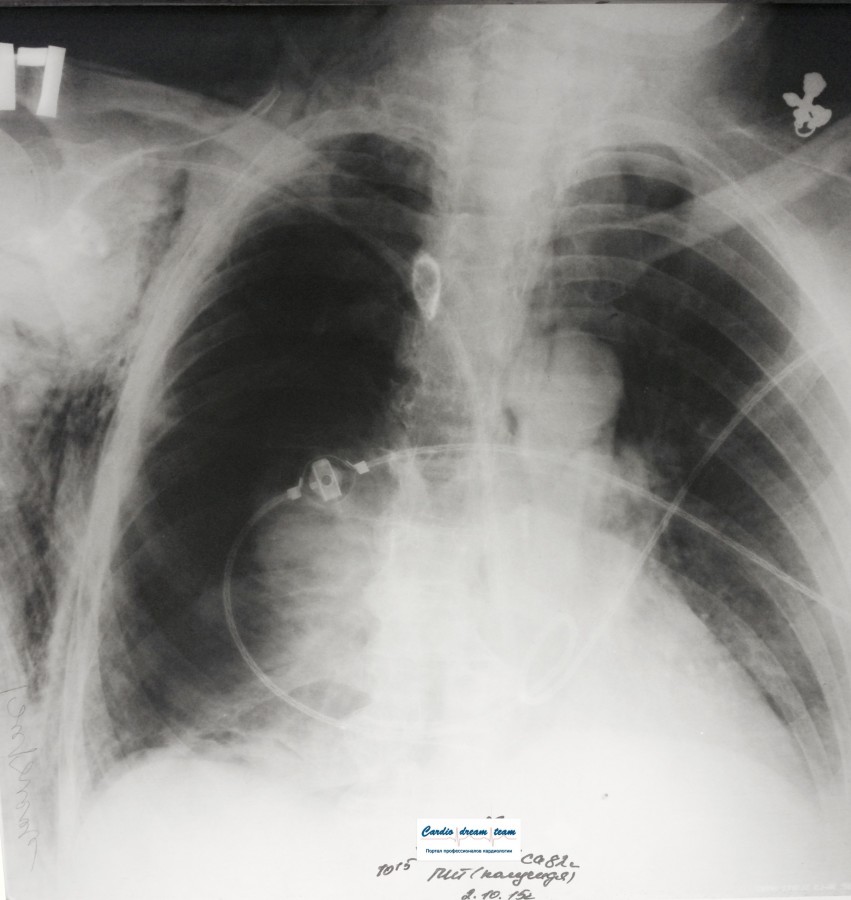

Проведена рентгенография органов грудной клетки в прямой проекции, положение полусидя, условия ПИТ, Р-контроль Легочные поля: Отрицательная динамика: правое легкое поджато к корню. Тень средостения резко смещена влево. Выраженная подкожная эмфизема мягких тканей грудной клетки справа. Тень подключичного катетера в проекции ВПВ. Легочный рисунок: диффузно деформирован за счет пневмосклероза, сгущен справа Корни: тень средостения смещена влево Синусы: нечеткие Сердце: широко лежит на диафрагме (позиционно) ЗАКЛЮЧЕНИЕ: Правосторонний пневмоторакс, отрицательная Р-динамика. Эмфизема мягких тканей грудной клетки. Пневмосклероз. Р-контроль.